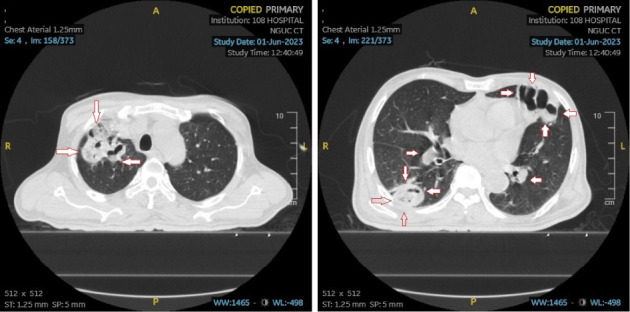

背景:Lemierre's syndrome (LS)是由Andre Lemierre在20世纪初首次描述的,是一种罕见但可能危及生命的疾病,通常由坏死梭杆菌引起。然而,最近的文献报道了由各种其他细菌引起的LS病例,包括肺炎克雷伯菌。在本报告中,我们提出了一例罕见的LS患者与糖尿病引起的肺炎克雷伯菌。病例报告:一名62岁越南男性,有2型糖尿病病史,表现为8天进行性左颈部肿胀、发热、吞咽困难、吞咽困难和食欲下降。尽管最初的抗生素治疗,他的病情恶化,导致肺脓肿和感染性休克。脓肿内容物培养显示肺炎克雷伯菌。患者需要插管、机械通气和颈部脓肿手术引流。美罗培南治疗和血糖控制导致临床改善。患者随后拔管,创面完全愈合,生化指标正常出院。结论:该病例强调了LS可能由Andre Lemierre最初未概述的病原体引起,例如肺炎克雷伯菌。当临床强烈怀疑LS时,临床医生应考虑更广泛的致病微生物,并相应地调整抗菌药物的覆盖范围。肺炎克雷伯菌相关的LS与糖尿病之间的关系值得进一步调查,因为目前的证据表明糖尿病可能使患者易患这种特殊病原体。

Background: Lemierre's syndrome (LS), first described by Andre Lemierre in the early 20th century, is a rare but potentially life-threatening condition typically caused by Fusobacterium necrophorum. However, recent literature has reported cases of LS caused by various other bacteria, including Klebsiella pneumoniae. In this report, we present a rare case of LS in a patient with diabetes caused by K. pneumoniae. Case Report: A 62-year-old Vietnamese male with a history of type 2 diabetes mellitus, presented with an 8-day history of progressive left neck swelling, fever, dysphagia, odynophagia, and reduced appetite. Despite initial antibiotic therapy, his condition deteriorated, leading to pulmonary abscesses and septic shock. Abscess content culture revealed K. pneumoniae. The patient required intubation, mechanical ventilation, and surgical drainage of the neck abscess. Treatment with meropenem, along with glycemic control, led to clinical improvement. The patient was subsequently extubated, achieved complete wound healing, and was discharged with normal biochemical parameters. Conclusion: This case highlights that LS can be caused by pathogens not initially outlined by Andre Lemierre, such as K. pneumoniae. Clinicians should consider a broader spectrum of causative organisms when there is a strong clinical suspicion of LS and adjust antimicrobial coverage accordingly. The association between K. pneumoniae-related LS and diabetes mellitus warrants further investigation, as current evidence suggests that diabetes may predispose patients to this particular pathogen.